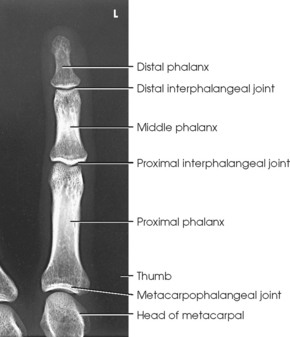

The digits contain 14 phalanges (phalanx, singular), which are long bones that consist of a cylindric body and articular ends. Nine phalanges have two articular ends. The first digit has two phalanges—the proximal and distal. The other digits have three phalanges—the proximal, middle, and distal. The proximal phalanges are the closest to the palm, and the distal phalanges are the farthest from the palm. The distal phalanges are small and flattened, with a roughened rim around their distal anterior end; this gives them a spatulalike appearance. Each phalanx has a head, body, and base.

The interphalangeal (IP) articulations between the phalanges are synovial hinge type and allow only flexion and extension (Fig. 4-8). The IP joints are named by location and are differentiated as either proximal interphalangeal (PIP) or distal interphalangeal (DIP), by the digit number, and by right or left hand (e.g., the PIP articulation of the fourth digit of the left hand) (Fig. 4-9, A and B). Because the first digit has only two phalanges, the joint between the two phalanges is simply called the IP joint.

The metacarpals articulate with the phalanges at their distal ends and the carpals at their proximal ends. The metacarpophalangeal (MCP) articulations are synovial ellipsoidal joints and have the movements of flexion, extension, abduction, adduction, and circumduction. Because of the less convex and wider surface of the MCP joint of the thumb, only limited abduction and adduction are possible.